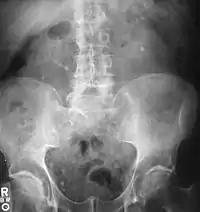

اکثر سنگها به دلیل ترکیبی از عوامل ژنتیکی و محیطی شکل میگیرند. عوامل خطر شامل کلسیم بالای ادرار، چاقی و کمتحرکی، غذاهای خاص، برخی داروها، مکملهای کلسیم، هیپرپاراتیروئیدیسم، نقرس و نوشیدن مایعات ناکافی است. سنگها در کلیه به خاطر غلظت بالای مواد معدنی در ادرار تشکیل میشوند. تشخیص معمولاً بر اساس علائم، آزمایش ادرار و تصویربرداری پزشکی است. آزمایش خون همچنین ممکن است مفید باشد.[2] سنگها بهطور معمول براساس موقعیت آنها طبقهبندی میشوند: سنگ کلیه (nephrolithiasis)، سنگ مجاری (ureterolithiasis)، سنگ مثانه (cystolithiasis). طبقهبندی دیگر بر اساس مادهای است که سنگ از آن تشکیل میشود: اگزالات کلسیم، اسید اوریک، استرویت، سیستین؛ البته اغلب سنگها از جنس کلسیم اُگزالات هستند.[1]

تشخیص[6]

اگر یک یا چند مورد از علائم ذکر شده را در خود مشاهده میکنید، باید به پزشک متخصص اورولوژی مراجعه کنید. پس از انجام آزمایشهای تخصصی، وجود یا عدم وجود آن، توسط پزشک تشخیص داده شده و سایر اقدامات لازم برای شما تجویز خواهد شد.